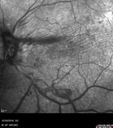

Sickle Retinopathy - Chronic retinal detachment OS - Proliferation OD396 views40 year old with known SC disease. Failed to return 4 years ago for treatment and lost ision in the left eye. Then returned for one visit and refused further treatment.Jan 28, 2019

|